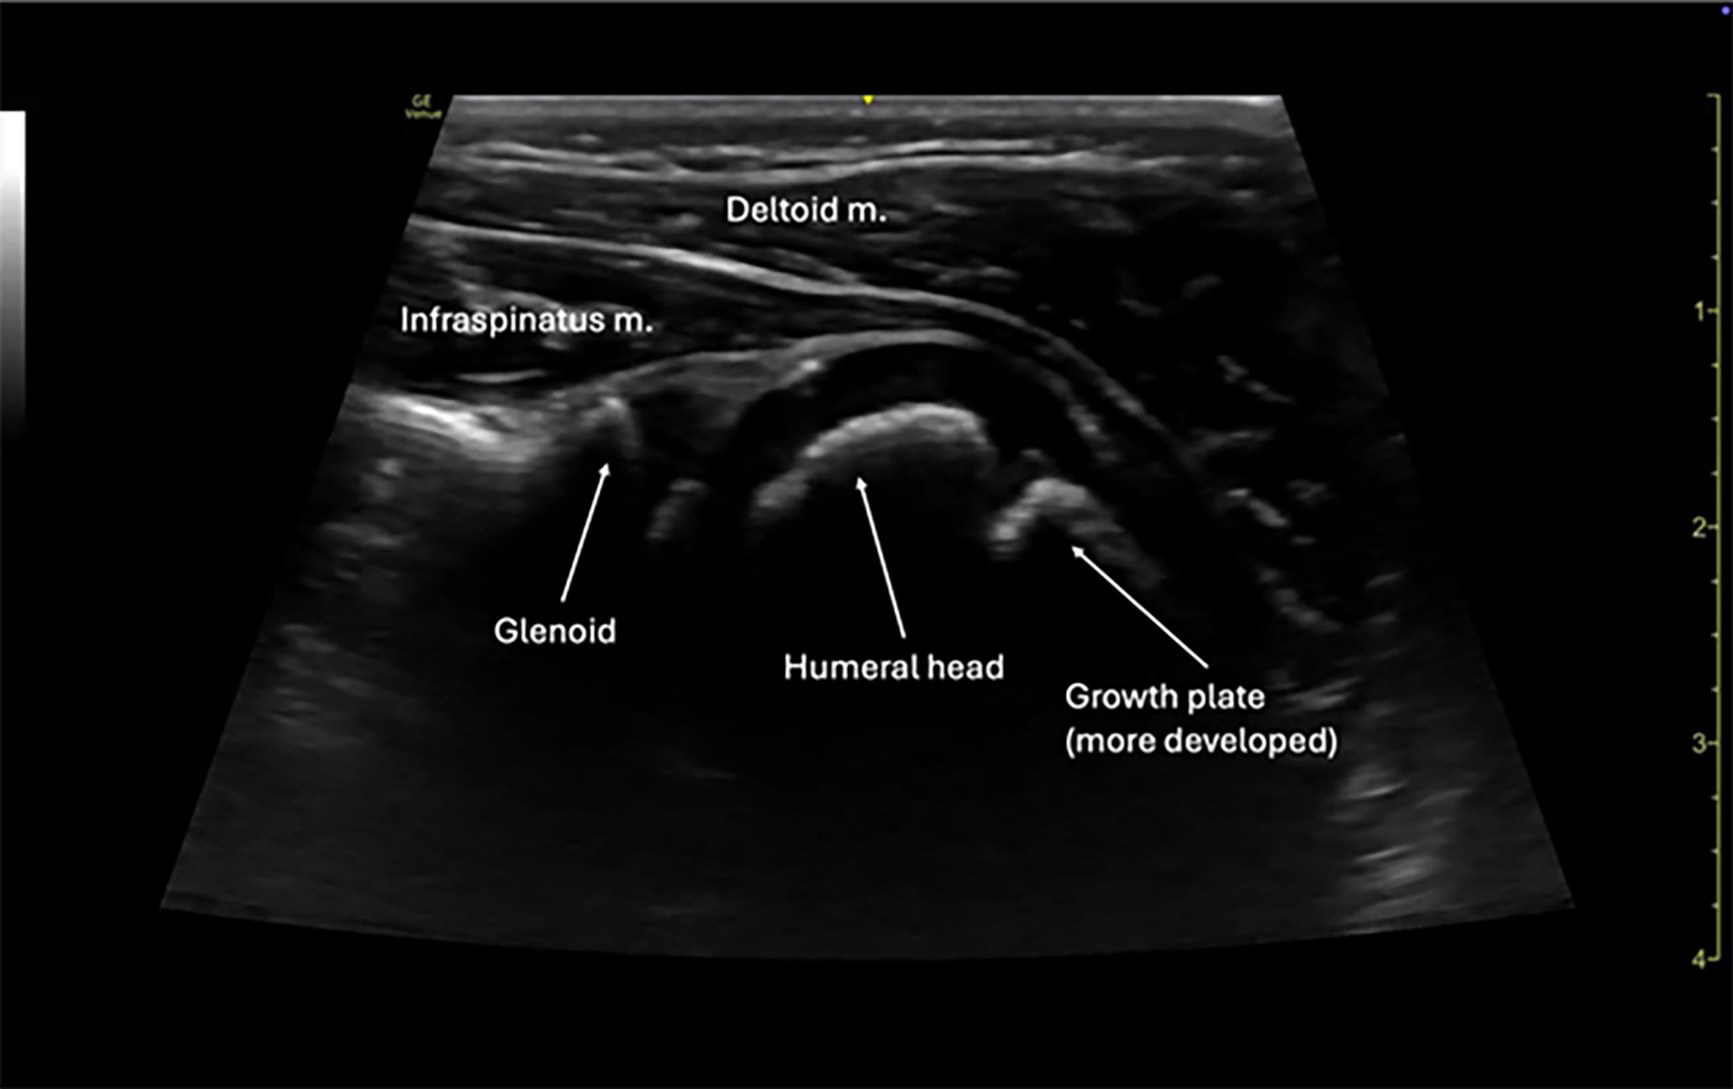

The posterior approach to shoulder ultrasound is the preferred technique for evaluating suspected dislocations. With the patient seated or in the lateral decubitus position, place a high-frequency linear probe transversely on the posterior aspect of the shoulder, just inferior to the scapular spine. The probe marker should point laterally. Identify the glenoid fossa and humeral head. In a normal (reduced) shoulder, the humeral head will sit congruently within the glenoid. (See Figures 6 and 7.) In an anterior dislocation, the humeral head will appear displaced anteriorly (and thus deeper on the screen), while in a posterior dislocation it will lie posteriorly and more superficial.

Figure 6. Normal Shoulder View |

3-year-old male via linear probe |

![]() |

Image courtesy of: Matthew D. Holmes, MD. |

Figure 7. Normal Shoulder View |

5-year-old female via linear probe |